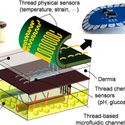

Breakthroughs in Nanotechnology

09/27/16 Advances in nanotechnology are revolutionizing medicine. A leader in the field describes recent developments and his commitment to making them available to a wide public. Sameer Sonkusale

How Nanotechnology is Revolutionizing Medicine

01/21/20 The unique features of the nano-scale are revolutionizing medical research and medical care. Here is the why and the how of that revolution. Sameer Sonkusale

Nanotechnology Advances for Healthcare and Environment

05/08/18 Truly innovative research: nano-tech devices for medicine and environment. Sameer Sonkusale

Nanotechnology in Medicine

04/20/17 A tour of some innovative medical nano-devices at the Tufts University Nano Lab. Sameer Sonkusale